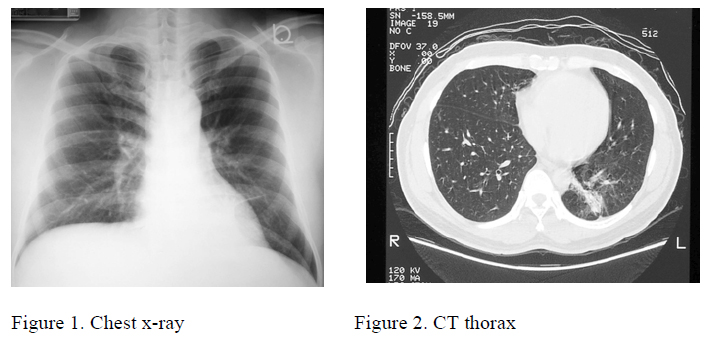

On physical examination he had normal body built. There was no clubbing of fingers. Chest examination was unremarkable alongside with other systems. Chest x-ray showed a retrocardiac shadow (Figure 1).

Blood tests showed normal haemoglobin. There was no systemic leucocytosis and the differential count showed normal level of eosinophil. Biochemistry for liver and renal function tests was unremarkable. Multiple sputum specimens showed negative findings for cytology examination and no acid fast bacilli were identified. CT thorax revealed a shadow at posterior basal segment of left lower lobe (figure 2).